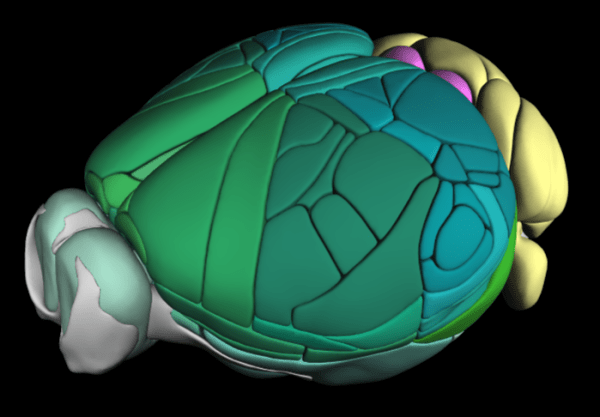

Mapping the Brain

A 3D map gives researches a better look into the mouse brain